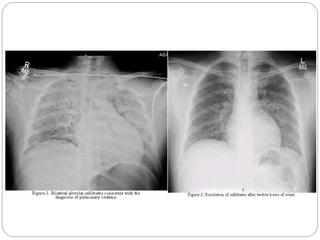

 The incidence of post-obstructive pulmonary oedema

 The common pattern is an episode of airway

obstruction at emergence followed by rapid onset of

respiratory distress, haemoptysis, and bilateral

radiological changes consistent with pulmonary

oedema.

 Both clinical and radiological features usually resolve

within 24 h with no sequelae, although delayed

presentation of up to 24 h, and progression to acute

lung injury and death have also been reported.